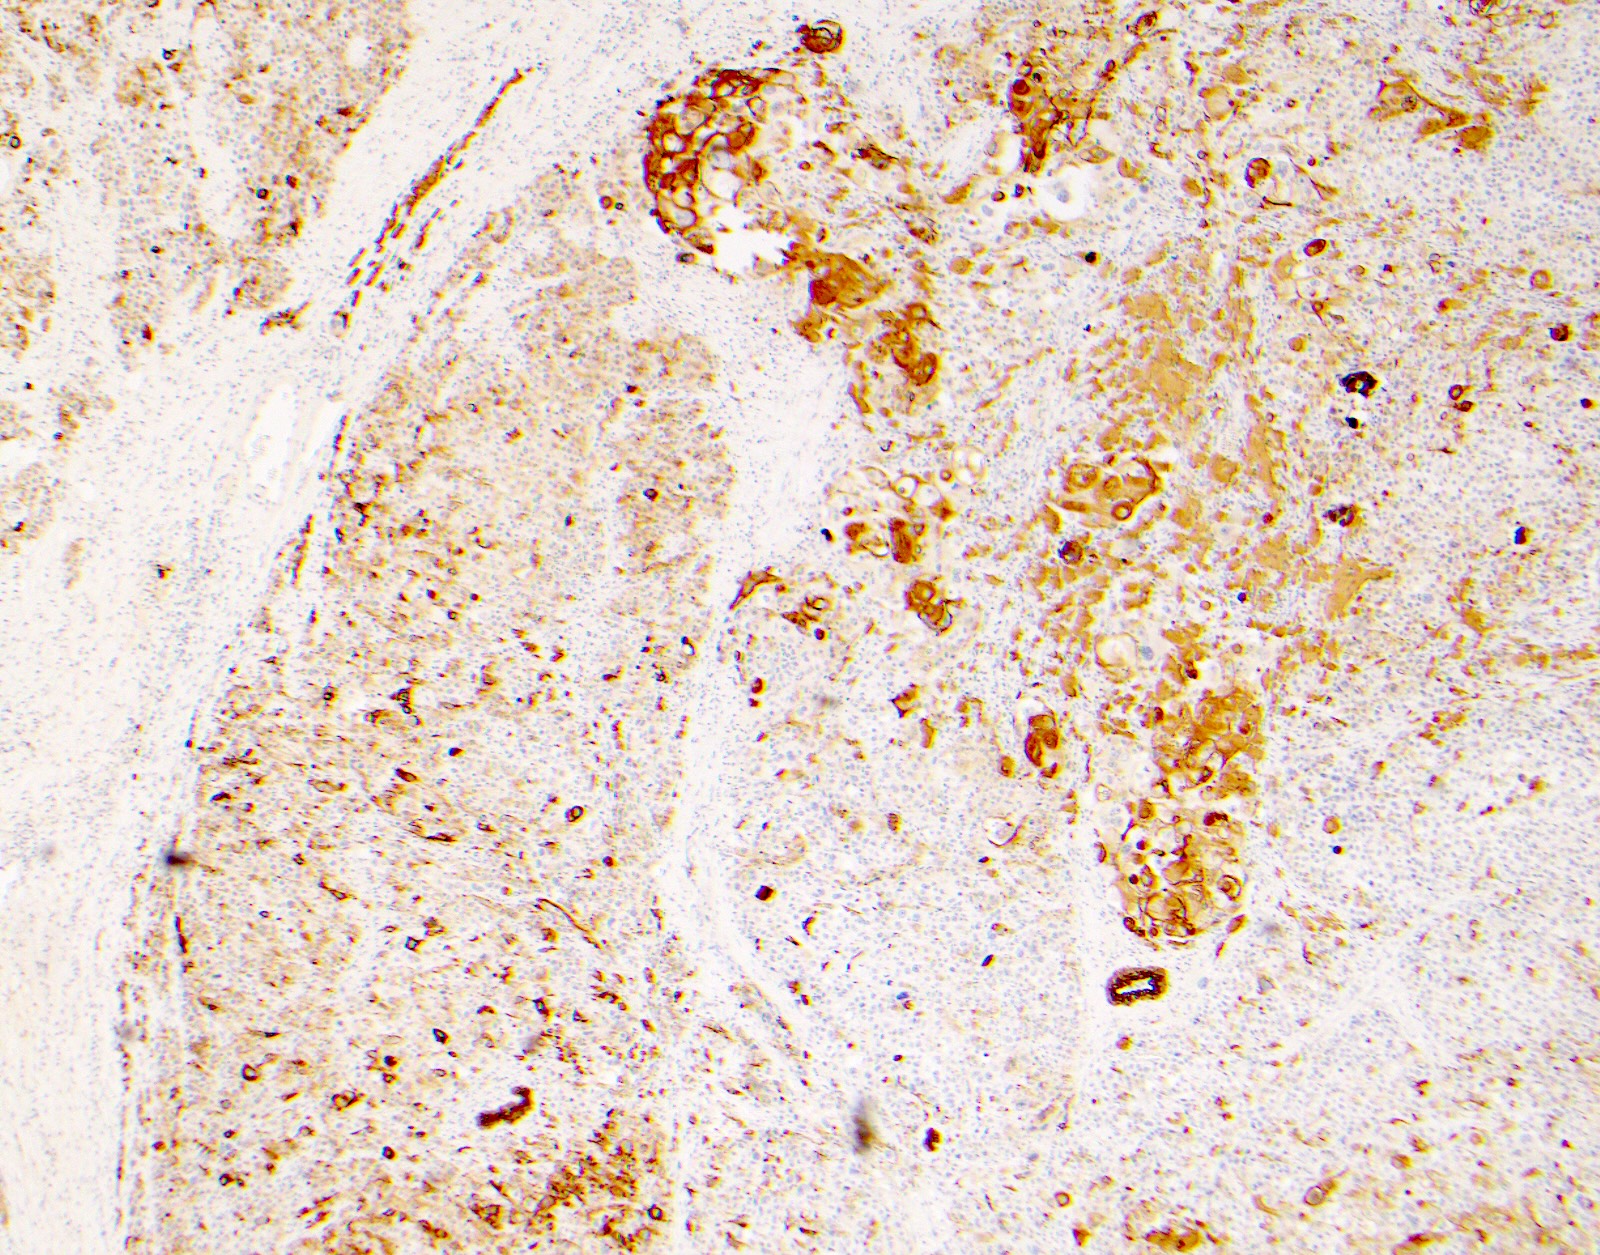

Microscopic (histologic) images

Contributed by Surekha Bantumilli, M.D. and Dimitri G. Trembath, M.D., Ph.D.

Positive staining - disease

- Breast ductal hyperplasia and lobular intraductal neoplasia (J Histochem Cytochem 2003;51:1527, Am J Surg Pathol 1999;23:1048)

- Prostatic basal cell hyperplasia (Hum Pathol 2003;34:462)

- Identification of the basal cell layer in prostate tissue in the determination of carcinoma

Practice question #1

A 65 year old man presents with elevated prostate specific antigen (PSA) and undergoes a prostate biopsy, stained with high molecular weight cytokeratin (HMWCK) (shown above). What is the most likely interpretation of this staining pattern?

- Benign prostate tissue

- Benign seminal vesicle

- High grade prostatic intraepithelial neoplasia

- Prostatic adenocarcinoma

- Urothelial carcinoma

Practice answer #1

A. Benign prostate tissue. The basal layer of benign prostate glands will stain with high molecular weight cytokeratin. Answer D is incorrect because staining will be lost on prostatic adenocarcinoma. Answer C is incorrect because high molecular weight cytokeratin staining can be present in high grade prostatic intraepithelial neoplasia but is not diagnostic by itself for this entity. Answers B and E are incorrect because the glandular appearance outlined by the high molecular weight cytokeratin staining is not consistent with either seminal vesicle or urothelial carcinoma.